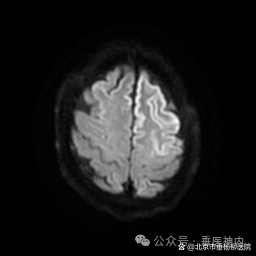

所有怀疑克-雅病诊断的患者,常规要进行脑脊液14-3-3蛋白检测;有条件的医疗机构,做脑脊液和(或)皮肤RT-QuIC检测。同时,血和脑脊液总tau蛋白、磷酸化tau蛋白/总tau蛋白比值有助于克-雅病的诊断及鉴别诊断。脑电图常出现特异性的周期性尖慢复合波。头核磁DWI相可见特异性地沿皮质沟回走行的带状和(或)双侧基底核区的异常高信号。

我科收治的两例患者脑电图一例是漫波背景,一例可见尖慢复合波,两例患者DWI影像均可见至少两个皮质区域沿皮质沟回走行的带状异常高信号,一例进行了脑脊液14-3-3蛋白检测,一例进行了血和脑脊液总tau蛋白、磷酸化tau蛋白/总tau蛋白比值检测,结果均高度提示患者为克-雅病可能性大。

典型头核磁结果: